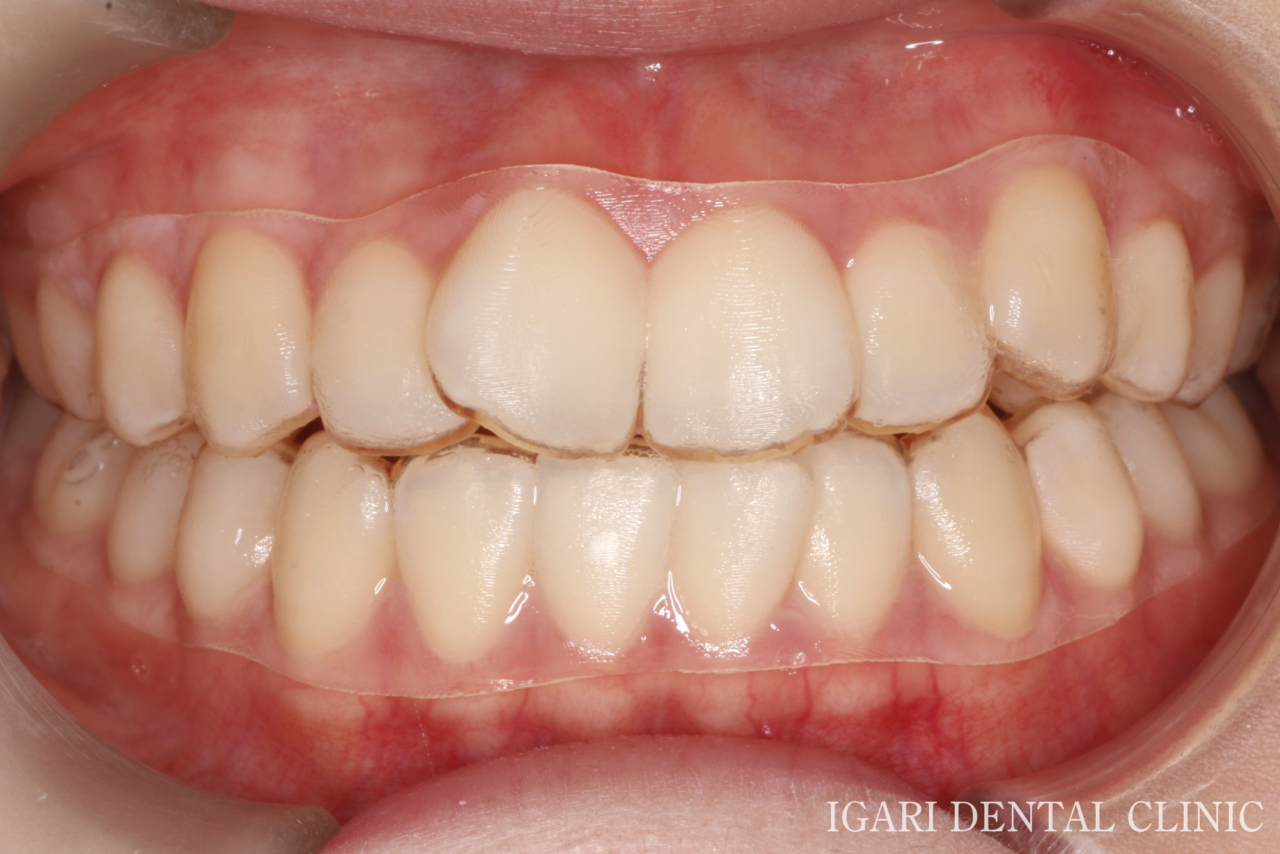

前歯の歯並びだけでなく、お口全体の歯並びと噛み合わせのバランスも整いました。

本症例ではアタッチメントを使用せずに治療を進めたため、歯の表面の見た目への影響が少なく、スマイル時の歯並びも自然に整いました。 -